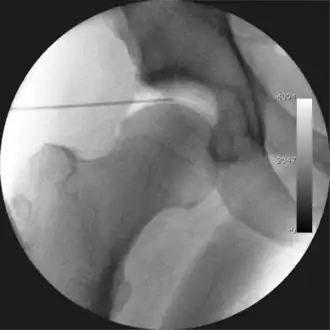

Figure 5. Portal placement under direct vision. The instrument is entering the joint through the hip capsule, between the femoral head (on the left) and acetabular labrum (on the right)

The next step is to insert a fine needle under x-ray guidance into the hip joint. This breaks the 'suction seal' of the joint and allows further distraction if necessary (see fig 4). The surgeon wishes to see the ball move out the socket by approximately 1 cm, so that access to the hip joint can be achieved with minimal risk of damage to the joint surfaces. Most surgeons will inject fluid into the joint at this stage, again to ensure that there is enough space between the ball and socket for safe instrument access. This needle is then removed. The next step is placement of the 'portals', or the small holes made to pass instruments into the joint. This is achieved by again passing a fresh hollow needle into the joint under x-ray control, usually in a slightly different position. The reason for this is so the surgeon can ensure that the needle, and subsequent cannulae do not penetrate and damage the acetabular labrum or cartilage joint surfaces (see fig. 5). Again, surgeons will have their own preferences as to their preferred placement. Through this hollow needle, a long thin flexible guide wire is passed into the joint, and the needle is removed over it, leaving the guide wire in situ. A small cut in the skin is made around the wire, to allow for larger cannulae to be placed over the wire through the portal. The wire therefore guides the larger cannulae into the joint. The most common external diameters of cannulae used are between 4.5 and 5.5 mm. Once the surgeon is satisfied that the cannula is in the correct position, by a combination of feel and x-ray guidance, the guide wire can be withdrawn. Once the first portal is correctly placed, any further portals may be created once the camera is in position, to ensure that they are placed with minimal risk to the joint surfaces. This process can be repeated to gain as many points of entry to the hip joint as the surgeon requires, normally between two and four. Certain of these entry points will be used for the viewing arthroscope and others for operating instruments.